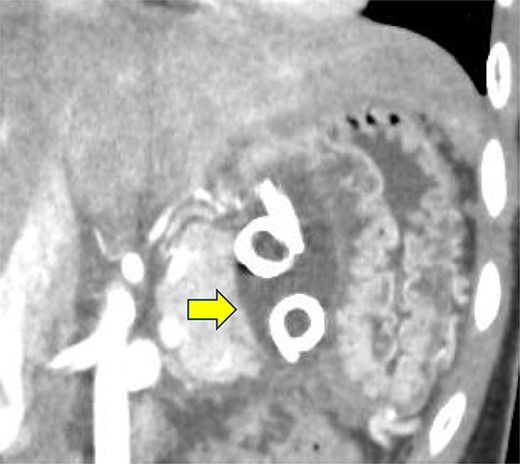

A 19-year-old woman who had fallen from a bicycle and bruised her upper left abdomen with handlebars presented to our emergency department 18 h after the injury with persistent abdominal pain. She was admitted with a diagnosis of pancreatic injury, as evidenced by elevated pancreatic amylase (P-Amy) levels (779 IU/L) and contrast-enhanced computed tomography (CT) showing a linear area with poor contrast in the pancreatic body (Fig. 1). Physical examination revealed a flat abdomen with mild tenderness in the upper left quadrant. Biochemical blood tests revealed elevated inflammatory markers; white blood cell count 10 950/μl, and C-reactive protein 0.58 mg/dl. On the fourth day, white blood cell count elevated to 21 940/μl and C-reactive protein elevated to 32.7 mg/dl. Contrast-enhanced CT revealed fluid accumulation, indicating pancreatic pseudocyst, primarily in the ventral pancreatic body and extending toward the spleen, along with edematous thickening of the adjacent stomach wall (Fig. 2).

Contrast-enhanced CT of the abdomen on the fourth day. Fluid accumulation (pancreatic pseudocyst) was observed, primarily located on the ventral pancreatic body and extending toward the vicinity of the spleen, along with edematous thickening of the adjacent gastric posterior wall.